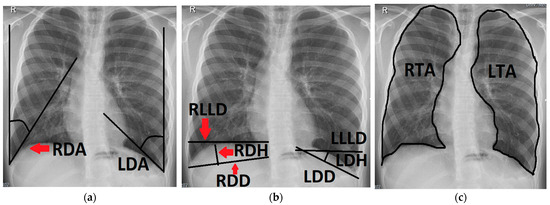

Figure 2.

Chest radiograph of a 16-year-old patient after left-sided CDH repair with a cone-shaped patch in the neonatal period; measurements of the following variables are outlined (black line) and labeled on the patient’s right side (red arrows): (a) right and left diaphragmatic angle (RDA, LDA); (b) right and left diaphragmatic diameter (RDD, LDD), right and left diaphragmatic height (RDH, LDH) and right and left lower lung diameter (RLLD, LLLD); (c) right and left thoracic area (RTA, LTA).

- The left and right diaphragmatic angle (LDA, RDA), which were defined by the angle between the lateral chest wall and the tangent to the convex side of the ipsilateral diaphragm coming from the costodiaphragmatic recessus.

- The left and right diaphragmatic diameter (LDD, RDD), measuring from the costodiaphragmatic recessus to the medial limit of the diaphragm.

- The left and right diaphragmatic height (LDH, RDH), measured as the perpendicular line from the diaphragmatic diameter to the apex of the diaphragm.

- The left and right lower lung diameter (LLLD, RLLD), measuring the width of the lung from its limit at the lateral chest wall to its medial limit at the level of the apex of the diaphragm.

- The left and right thoracic area (LTA, RTA) were defined by delineating the outer border of the lung tissue, excluding the mediastinum and the cardiac shadow.

- The left and right diaphragmatic curvature index (LDCI, RDCI) were calculated via the quotient of the diaphragmatic diameter and the diaphragmatic height (e.g., LDD/LDH = LDCI). A large LDCI therefore indicates a flat diaphragm with only a small curvature.